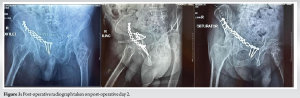

The management of acetabular fractures poses a significant dilemma in choosing between operative and non-operative treatment modalities. In our case, considering the age, bone quality, comminution of the fracture, need for anatomical fixation, and early mobilization, we opted for ORIF. The patient was taken to surgery within 48 h of injury after obtaining anesthesia fitness. Under spinal and epidural anesthesia, the patient was positioned in the supine position, using modified Stoppa’s approach, and the patient underwent ORIF with a 12-hole suprapectineal plate and appropriate screws. Intraoperatively, the impacted fragment and central dislocation were reduced and fixed with this special suprapectineal plate, which also buttresses the quadrilateral plate. Intraoperatively, the reduction was found to be satisfactory under C-Arm guidance. Post-operative X-ray was done on post-operative day 2, which showed excellent reduction (Fig. 3).